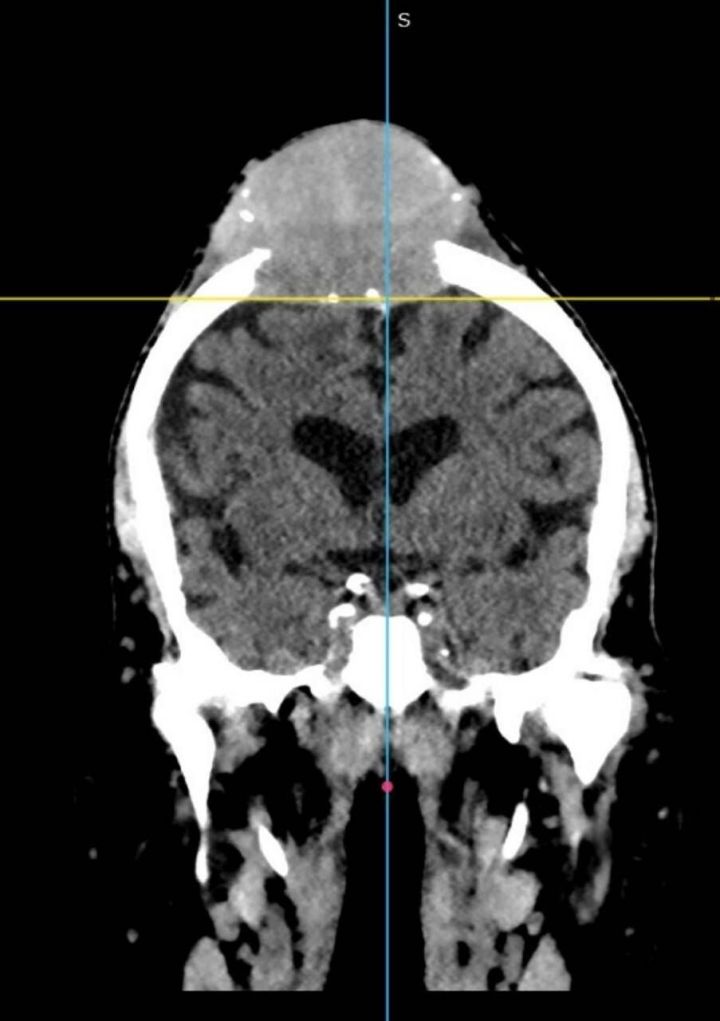

11 ноября в Республиканскую клиническую больницу Татарстана поступил 78-летний мужчина с постоянно растущим образованием на голове

В 2016 году мужчина перенес операцию по поводу рака правой почки, наблюдался у онколога. В декабре прошлого года заметил, что на голове растет шишка.

«По направлению из ЦРБ прошел обследования в РКОД, откуда его направили на удаление образования к нам. 13 ноября нейрохирурги РКБ Татарстана удалили образование и сделали пластику титановой сеткой», — объяснили в РКБ Татарстана.

Гистология показала, что в голове вырос метастаз рака почки.